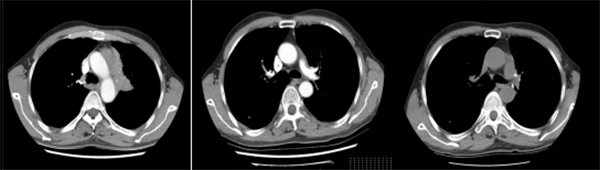

化疗带来的恶心、呕吐、脱发等副作用,让老陈备受折磨,但他从未中断治疗。“家人每天变着花样做我爱吃的,孩子们总说‘爸再坚持坚持’,我不能辜负他们。”老陈说。三个月后,复查结果传来喜讯:病灶体积缩小60%,达到手术指征。2019年春,老陈被推进手术室,家人在门外焦灼等待了5个小时,当主刀医生走出手术室说出“手术非常成功”时,妻子当场红了眼眶,紧紧攥着的手心全是汗水。

治疗前、手术前、手术后的胸部CT